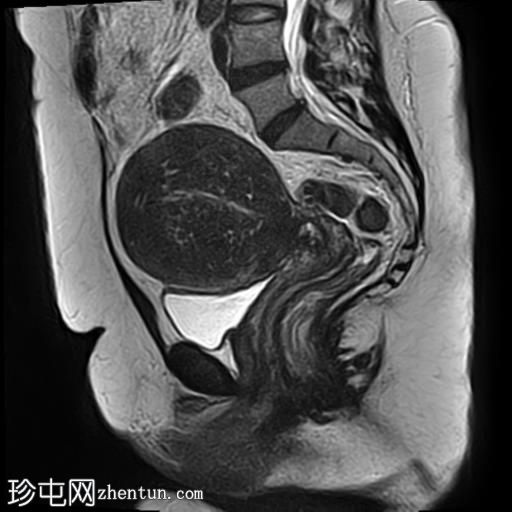

矢状位

T2加权像

子宫增大,子宫内膜-肌层交界区弥漫性增厚,T1加权像呈中等信号,最高达45 mm;T2加权像呈低信号,内含多个小的高T2信号灶,提示月经出血渗入异位子宫内膜组织,符合弥漫性子宫腺肌症的

影像

学表现。

卵巢可见多个小的单房囊肿,无分隔或实性成分,最可能是浆液性包涵囊肿。

MRI表现最符合弥漫性子宫腺肌症。